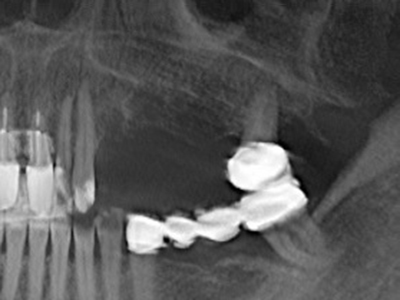

cazione: rialzo del seno

La preparazione della finestra laterale durante un rialzo del pavimento sinusale esterno è complicata, in particolare per gli implantologi con poca esperienza chirurgica. La rimozione della copertura ossea del seno senza danneggiare la membrana schneideriana sottostante è solo una parte dell'operazione: dopo aver stabilito un accesso adeguato, la membrana interna del seno deve essere spostata con cautela per far spazio ai materiali di accrescimento o agli impianti. La piezochirurgia è utile per questa indicazione in due modi: è possibile utilizzare gli strumenti diamantati per l'ablazione selettiva dell'osso e, se la procedura viene eseguita con precisione, la membrana mucosa sottostante rimane intatta. Le frequenze ultrasoniche permettono anche la separazione della membrana mucosa senza complicanze: le frequenze vengono trasmesse nello spazio compreso tra la membrana mucosa e il pavimento sinusale mediante degli speciali raccordi smussati (Cassetta, Ricci et al. 2012, Pereira, Gealh et al. 2014) (Rickert, Vissink et al. 2013). Di conseguenza, non sorprende che le rivisitazioni attuali del rialzo del pavimento sinusale esterno valutino positivamente l'utilizzo dei dispositivi piezoelettrici, delle superfici non lisce degli impianti e dei materiali di riempimento dell'osso (Wallace, Tarnow et al. 2012).